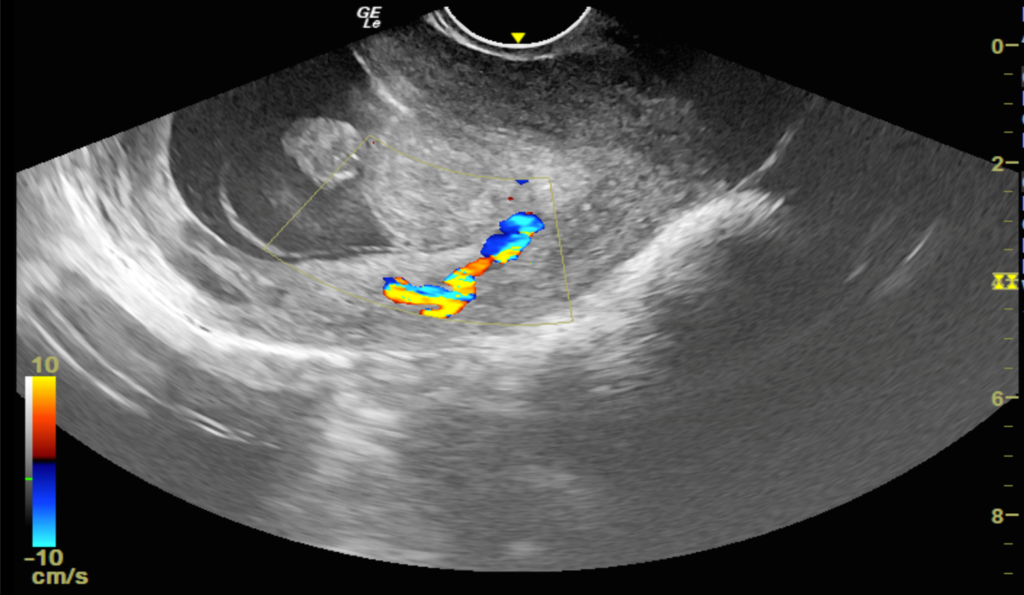

We report a case of a 24-year-old lady who was unable to conceive for a period of 8 years. Infertility workup was negative. In 2018, she conceived, however cardiac activity was not demonstrated in the fetus and eventually medical abortion was performed. Transvaginal sonography was performed for the same at a private center which did not pick up any uterine structural abnormality. In 2021, the patient presented to our emergency department with a 14-week gestation pregnancy with complaints of bleeding per vaginum for 2 days. Antenatal transvaginal ultrasound was performed for confirmation and viability of an intrauterine pregnancy. An intrauterine gestational sac with crown rump length corresponding to 8 weeks 5 days and absent cardiac activity was seen suggesting the diagnosis of missed abortion (Figure 1). Surrounding the gestational sac was fluid with internal echoes suggesting failure of implantation (Figure 2). A well-defined uniformly echogenic pedunculated lesion was seen in the endometrial cavity (Figure 3). As it was traced towards the point of its origin, a focally hypoechoic region was demonstrated interrupting the hyperechoic endometrial lining (Figure 4), classically described as the ‘interrupted mucosa sign’ [2]. On colour doppler image, a single vascular pedicle was demonstrated (Figure 5), known as the ‘pedicle artery sign’ [3]. Based on these classical features the diagnosis of an endometrial polyp was made. It was seen to abut the gestational sac suggesting mechanical hindrance to growth of the embryo (Figure 6). On real time imaging, the endometrial polyp was seen prolapsing from towards the uterine fundus to the lower uterine segment (Figure 7). For better characterization of the endometrial polyp, it has been recommended to distend the uterine cavity with saline (also known as saline infusion sonohysterography) [4,5], however in our case it was unwarranted because the gestational sac and fluid naturally distended the uterine cavity and helped in optimum visualization (Figure 4,6). Figure 8 depicts another case of an endometrial polyp showing a non-gravid uterus with an echogenic lesion in the endometrial cavity showing the classical interrupted mucosa sign (Figure 8A) and the feeding artery sign (Figure 8B).

Figure 5: Color doppler images show a single feeding artery supplying the stalk of polyp, described as ‘pedicle artery sign’.